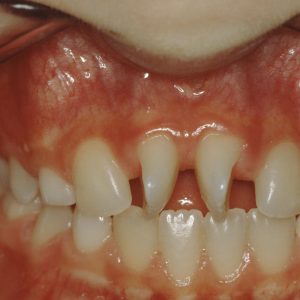

90° rotated incisors